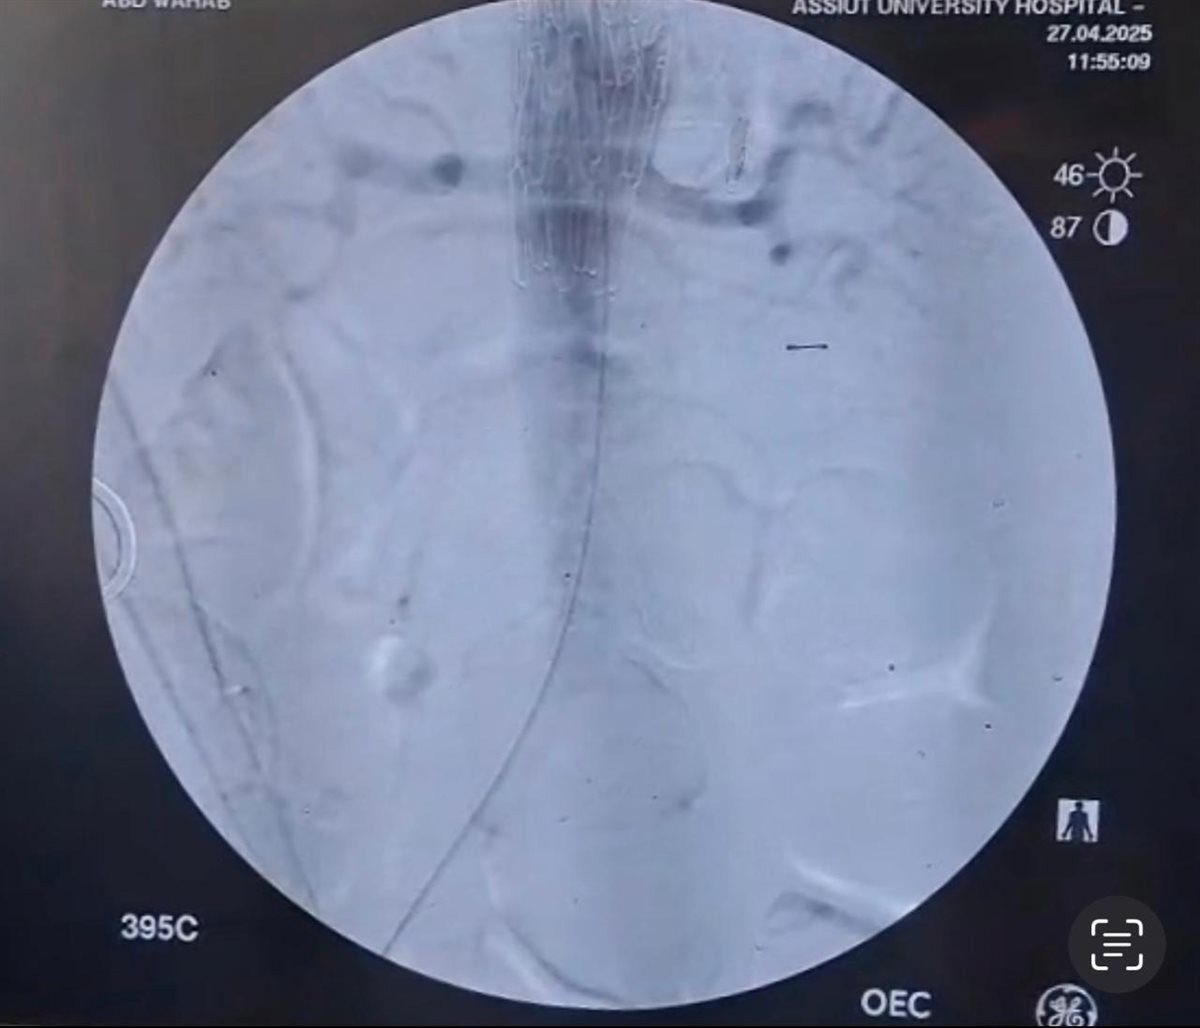

بينما تضمنت المرحلة الثانية استخدام القسطرة التداخلية بعد تخطيط دقيق وتنسيق وثيق بين التخصصات المختلفة، حيث قام الفريق الطبي بقسم جراحة الأوعية الدموية بالمستشفى الجامعى الرئيسى تحت إشراف الدكتور خالد عبد العزيز مدير المستشفى، وبرئاسة الدكتور هيثم علي حسن رئيس القسم، وضم كلا من: الدكتور محمود إسماعيل، أستاذ جراحة الأوعية الدموية، والطبيب أحمد نجيب، مدرس مساعد بالقسم، بإجراء إصلاح للانشطار بالشريان الأورطي الصدري والبطني باستخدام القسطرة التداخلية وتركيب دعامات مغطاة باستخدام تقنية (TEVAR).

وعقب ذلك قامت الدكتورة سلمى طه، أستاذ مساعد بقسم القلب، باستخدام تقنية التحفيز البطيني السريع من خلال تركيب منظم ضربات قلب مؤقت بالبطين الأيمن، والذى ساهم في تقليل حركة جدار الشريان الأورطي لزرع الدعامة المغطاة بالشريان الأورطي بدقة.